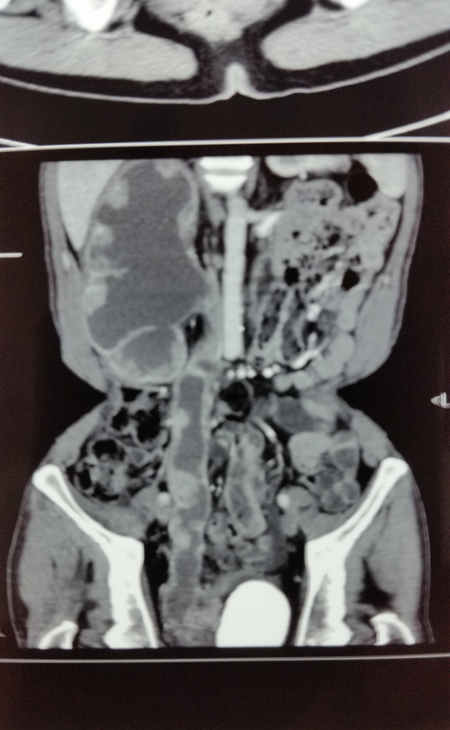

在全方位开展微创新技术的同时,泌尿外科并没有放松和抛弃传统开放手术这一看家本领。今年6月,王金根博士为一位罕见的肾、输尿管、膀胱多发性肿瘤患者成功实施了传统开放切除手术,一次性完整切除右肾、右输尿管和全膀胱,术后没有并发症,病理切片证实为腺癌,各切缘均未见癌细胞(表明切除彻底)。患者是一位54岁男性,反复肉眼血尿2年多,右侧腰痛2个月,近期还伴有发烧。入院后经相关检查很快确诊了病情:右侧肾盂肾盏、右输尿管全长和膀胱内均生长了大量肿瘤,同时合并感染,膀胱内还有一个巨大结石,此外还存在严重贫血和营养不良,全身水肿。用传统开放手术方法切除肿瘤是患者目前唯一的治疗选择。由于肿瘤引起梗阻并在此基础上发生感染,如果不尽早切除肿瘤,患者的感染无法控制,患者短期内就会有生命危险。然而由于长期梗阻,右侧肾盂肾盏和输尿管重度扩张,加上近期合并感染,肾脏周围广泛粘连,手术分离过程中肾脏及输尿管壁极易破损,一旦破损将会导致肿瘤扩散,严重影响疗效,因此手术难度极大,风险很高,对手术医生的技术要求非常高。王金根博士组织全科专家反复讨论制定治疗方案,并亲自带领治疗组进行充分细致的术前准备。2014年6月9日,由王博士主刀,在全麻下为患者施行了手术。手术中发现患者右肾体积巨大,与腰背部肌肉、肝脏、结肠和下腔静脉等重要器官广泛紧密粘连,手术难度比术前估计的还要大。为了解除患者的病痛,挽救患者的生命,王金根博士、贾灵华和包佑根医生等组成的手术小组迎难而上,历经八个小时的艰苦努力,终于将患者的右肾、输尿管和膀胱完整切除,邻近器官完好无损,患者顺利康复出院。

CT扫描示右肾、右输尿管、膀胱多发性肿瘤,膀胱巨大结石